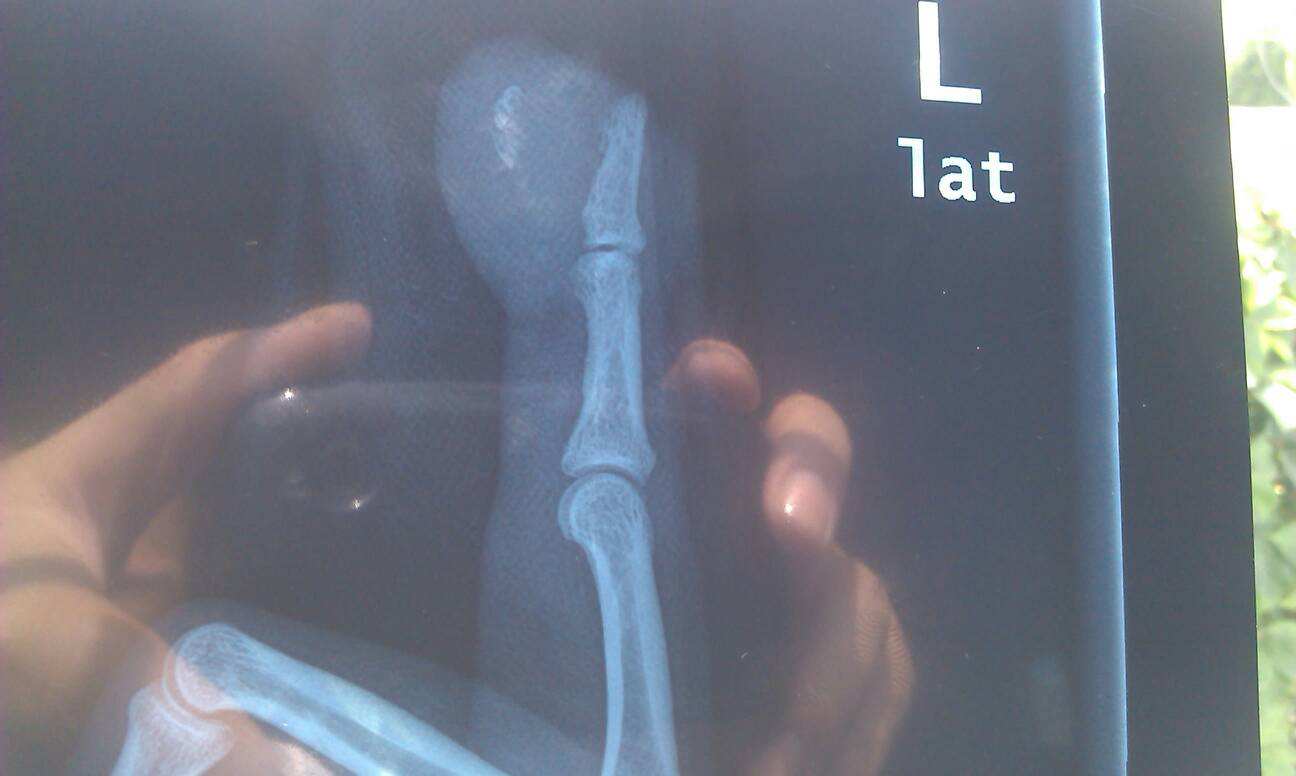

六、脊柱、骨盆及四肢损伤

1、枢椎齿状突骨折,影响功能;

2、一椎体压缩性骨折(压缩程度达1/3)或者粉碎性骨折;一椎体骨折经手术治疗后;

3、四处以上横突、棘突或者椎弓根骨折,影响功能;

4、骨盆两处以上骨折或者粉碎性骨折,畸形愈合;

5、一侧髌骨切除;

6、一侧膝关节交叉韧带、半月板伴侧副韧带撕裂伤经手术治疗后,影响功能;

7、青少年四肢长骨骨折累及骨骺;

8、一上肢前臂旋转功能丧失75%以上;

9、双上肢长度相差4.0cm以上;

10、双下肢长度相差2.0cm以上;

11、四肢任一大关节(踝关节除外)功能丧失25%以上;

12、一踝关节功能丧失50%以上;

13、下肢任一大关节骨折后遗创伤性关节炎;

14、肢体重要血管循环障碍,影响功能;

15、一手小指完全缺失并第5掌骨部分缺损;

16、一足拇趾功能丧失75%以上;一足5趾功能丧失均达50%;双足拇趾功能丧失均达50%;双足除拇趾外任何4趾功能均完全丧失;

17、一足跟骨粉碎性骨折畸形愈合;

18、一足足弓结构部分破坏;

19、手或者足功能丧失分值≥10分。